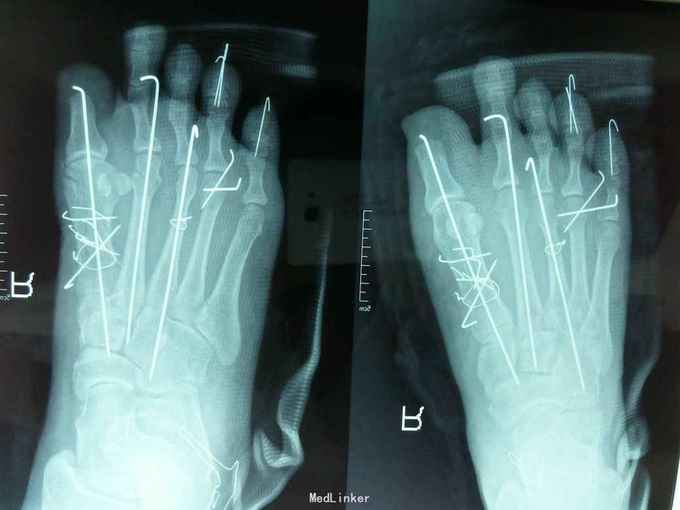

右足压砸伤 入院后完善相关住院及术前检查,急诊在腰麻下行‘右足清创、探查骨折复位内固定、踇趾残端修整术’,术后给予抗炎对症支持治疗。

术后病情平稳,愈合良好。